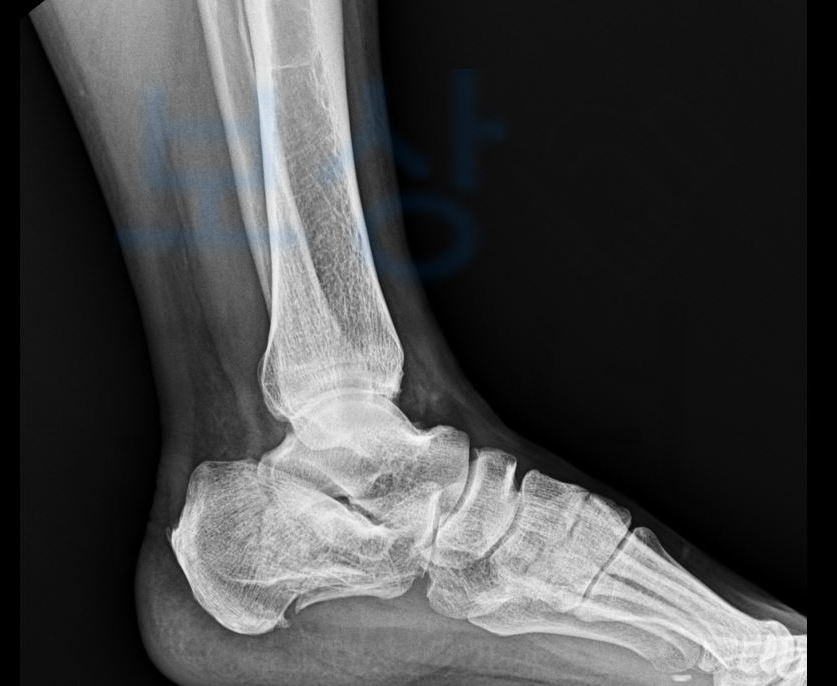

위 사고로 인해 엑스선상에 보이는

발 뒤꿈치 뼈의 골절 즉

좌측 종골의 분쇄골절 s92

정상인의 운동범위는 족관절 110도 이지만 의뢰인의 운동범위는 55도로 딱 1/2제한이었습니다.